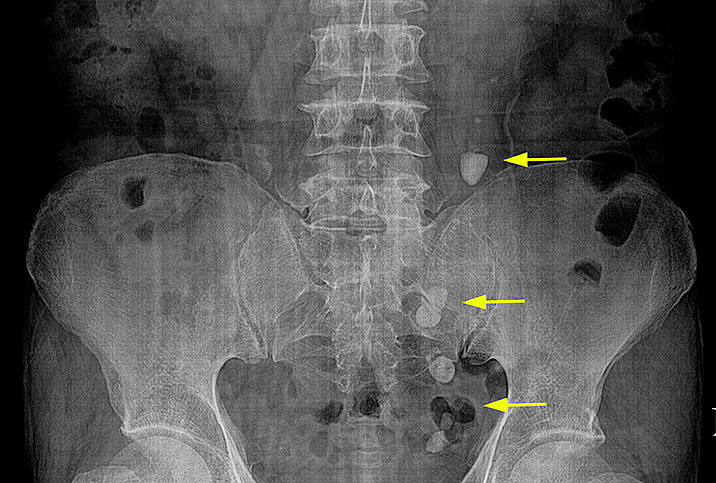

Рефлюксирующий мегауретер: Визуализация и медицинские изображения